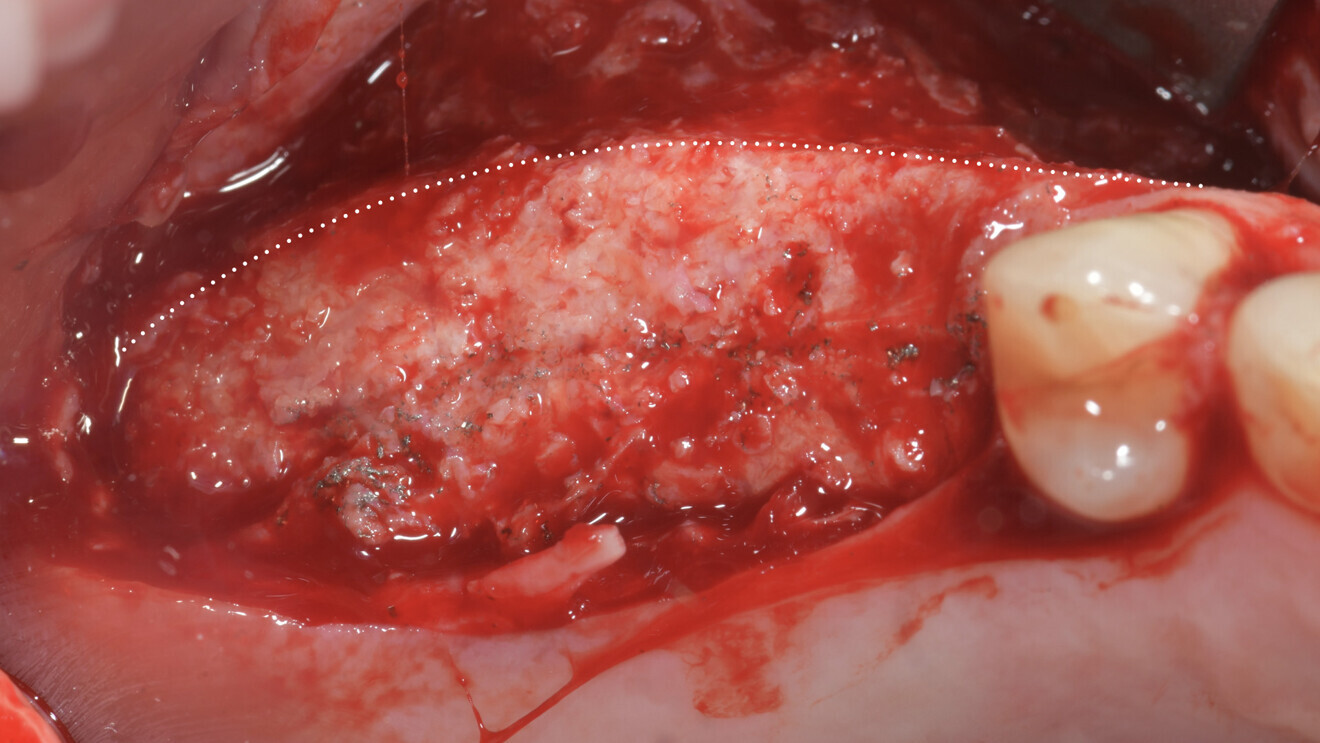

A horizontal incision was made along the mandibular ramus to harvest about 2 cm3 of autologous bone using a bone scraper (SafeScraper TWIST, Meta Technologies; Fig. 14a-d). The grafting material was then prepared by mixing a 50:50 ratio of autologous bone to deproteinised bovine bone matrix (Geistlich Bio-Oss, small granules), to which peripheral venous blood taken from the patient was added to promote coagulation (Figs. 15a-d).

Subsequently, the customised CAD/CAM titanium mesh (Yxoss CBR, ReOss) was taken from the double sterile pouch and filled with the grafting material (Figs. 16a & b). The mesh was then positioned in place and fixed with four osteosynthesis screws (BT screw, BTK) to achieve absolute stability (Figs. 17a & b). It was then covered with a native collagen resorbable membrane (Geistlich Bio-Gide), which was stabilised with titanium tacks (MCbio, Geistlich; Fig. 18).